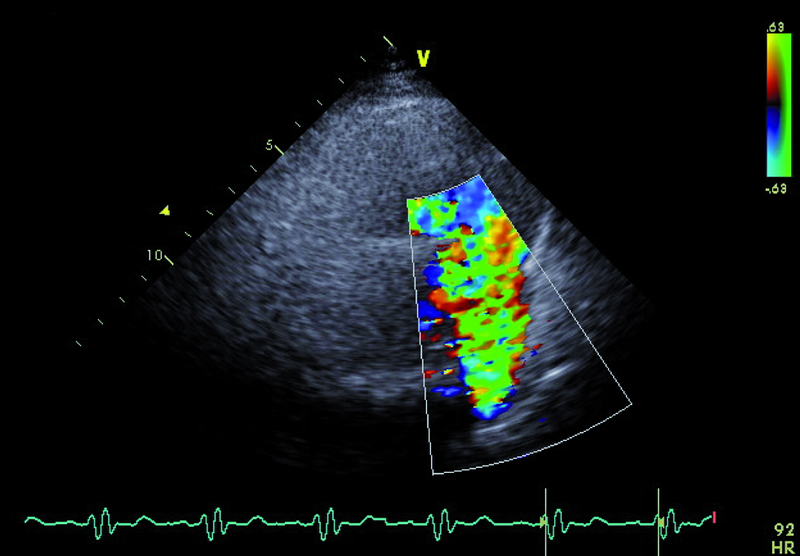

Droga odpływu prawej komory u opisanego chorego jest szeroka i z pewnością nie stanowi zapory dla przepływającej krwi (ryc. 1). Częstym powikłaniem całkowitej korekcji tetralogii Fallota, zwłaszcza z wykorzystaniem łaty przezpierścieniowej, jest duża niedomykalność zastawki płucnej, którą stwierdzono również u opisanego chorego. Strumień niedomykalności w badaniu kolorowego doplera jest szeroki i pokrywa prawie cały przekrój drogi odpływu (ryc. 2). Niedomykalność zastawki płucnej trudno ocenić ilościowo za pomocą techniki ultradźwiękowej. Złotym standardem diagnostyki jest rezonans magnetyczny, który pozwala określić tzw. frakcję niedomykalności. Spośród parametrów echokardiograficznych najbardziej zbliżonym i dość wiarygodnie odzwierciedlającym stopień niedomykalności zastawki płucnej jest czas połowicznego zmniejszenia gradientu ciśnień między pniem płucnym a prawą komorą (pressure half time, PHT). PHT krótszy niż 100 ms świadczy o istotnej niedomykalności zastawki płucnej (ryc. 3). Innym, nieanalizowanym w ilustracjach parametrem może być tzw. indeks niedomykalności, czyli iloraz czasu trwania fali zwrotnej płucnej do czasu trwania rozkurczu. Niedomykalność zastawki płucnej, nawet tak duża, jak w opisanym wypadku, nie musi istotnie ograniczać tolerancji wysiłku. W takiej sytuacji obowiązuje jednak precyzyjna ocena wielkości i funkcji prawej komory serca. Stopień powiększenia prawej komory u tego chorego jest umiarkowany (ryc. 4), a funkcja kurczliwa mięśnia mierzona za pomocą prędkości skurczowej ruchu bocznej części pierścienia trójdzielnego (S’) jest prawidłowa (ryc. 5). Dodatkowym parametrem łatwym do uzyskania niezwykle czułym w określaniu niedomogi prawej komory jest pole prawego przedsionka. Niewielkie przekroczenie górnej granicy normy, czyli 18 cm2, rejestrowane w tym przypadku (ryc. 6) potwierdza słuszność wyboru strategii zachowawczej. Chory może być nadal obserwowany, chyba że warunki anatomiczne drogi odpływu prawej komory pozwalają na przezcewnikową implantację zastawki Melody lub Edwards-Sapien. Określenie możliwości przeprowadzenia tego rodzaju interwencji ponownie wymaga jednak odniesienia się do wyników rezonansu magnetycznego lub wykonania cewnikowania serca.